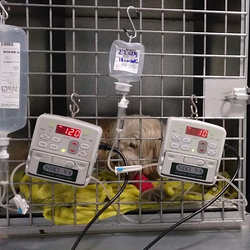

Hospitalizacion veterinaria

- Servicio de urgencias 24h